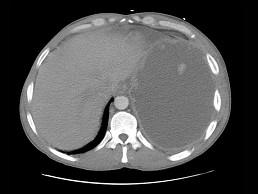

问题 43岁,男,持续高热一周,呼吸急促,胸痛,CT和胸片检查如图,请选出最可能的诊断 ( )

选项 A、肺气肿 B、胸膜间皮瘤 C、肺脓肿 D、气胸 E、脓胸

答案 E